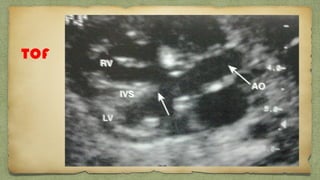

TOF